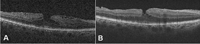

Cierre quirúrgico

El cierre quirúrgico en agujeros maculares completos se sitúa actualmente por encima del 90%, según la serie estudiada. Los factores que pueden afectar el cierre quirúrgico son

7 el tamaño de la lesión (de mejor pronóstico los de tamaño pequeño, menos de 400 µm), los signos de cronicidad y la técnica utilizada. Existen recomendaciones internacionales en cuanto a que la técnica de elección sería la vitrectomía pars plana, con disección de la membrana limitante interna y gas intraocular

17. No queda claro que la colocación en decúbito prono mejore los resultados

18 (

Figura 11).

Figura 11. Cierre quirúrgico de agujero macular de grosor completo. A) Imagen del paciente 2 años antes de desarrollar el agujero macular; se aprecia la existencia de una membrana epiretiniana sin apenas modificación de la anatomía macular. B) Agujero macular completo de pequeño tamaño (prácticamente los bordes se tocan), con levantamiento de los márgenes y edema quístico. C) Imagen 3 meses después de la cirugía mediante vitrectomía y pelado de la membrana limitante interna.